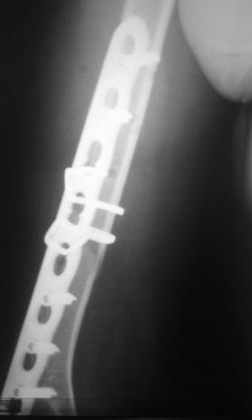

Перелом нестабильный, тактика - если позволяет сосояние больной, оперативное лечение. Как пример см. ниже, можно без скобы - стяжки с ЭПФ.

Представленный способ, функциональный, данная больная в качестве внешней иммобиллизации в течение 3-х недель полльзовалась косыночной повязкой, востановление функции плеча полное. Правда травма изолированная, но операция выполнялась через три недели после травмы, тот час после обращения ко мне - иногородняя.

Да, как раз блокированная пластина и стоит, не синтезовская метадиафизарная, Рыбинская, но на порядок дешевле, а профилактика всех осложнений - в данном конкретном случае, начало ранней на вторые сутки - после удаления дренажа разработки движений в смежных суставах. Если же идти с ревизией т.е. всё равно, открыто как вариант небольших разрезов при поперечном переломе можно и комбинированный мос (см.на вкладыше), хотя думаю для такого способа перелом всётаки низковат.

Всё правильно, просто я несколько разрозненно пытался сказать на частных примерах, то , что Вы систематизировали. Совершенно верно данный перелом можно и так и эдак, наиболее оптимально антеградное штифтование, хотя я бы предпочёл пластину LCP(просто - ну лучше у меня это получается и всё, а больному не вредит тот же функциональный способ). А низковато для неблокированного штифтования с конструкциями с термомеханической памятью, то, что представленно на втором снимке.